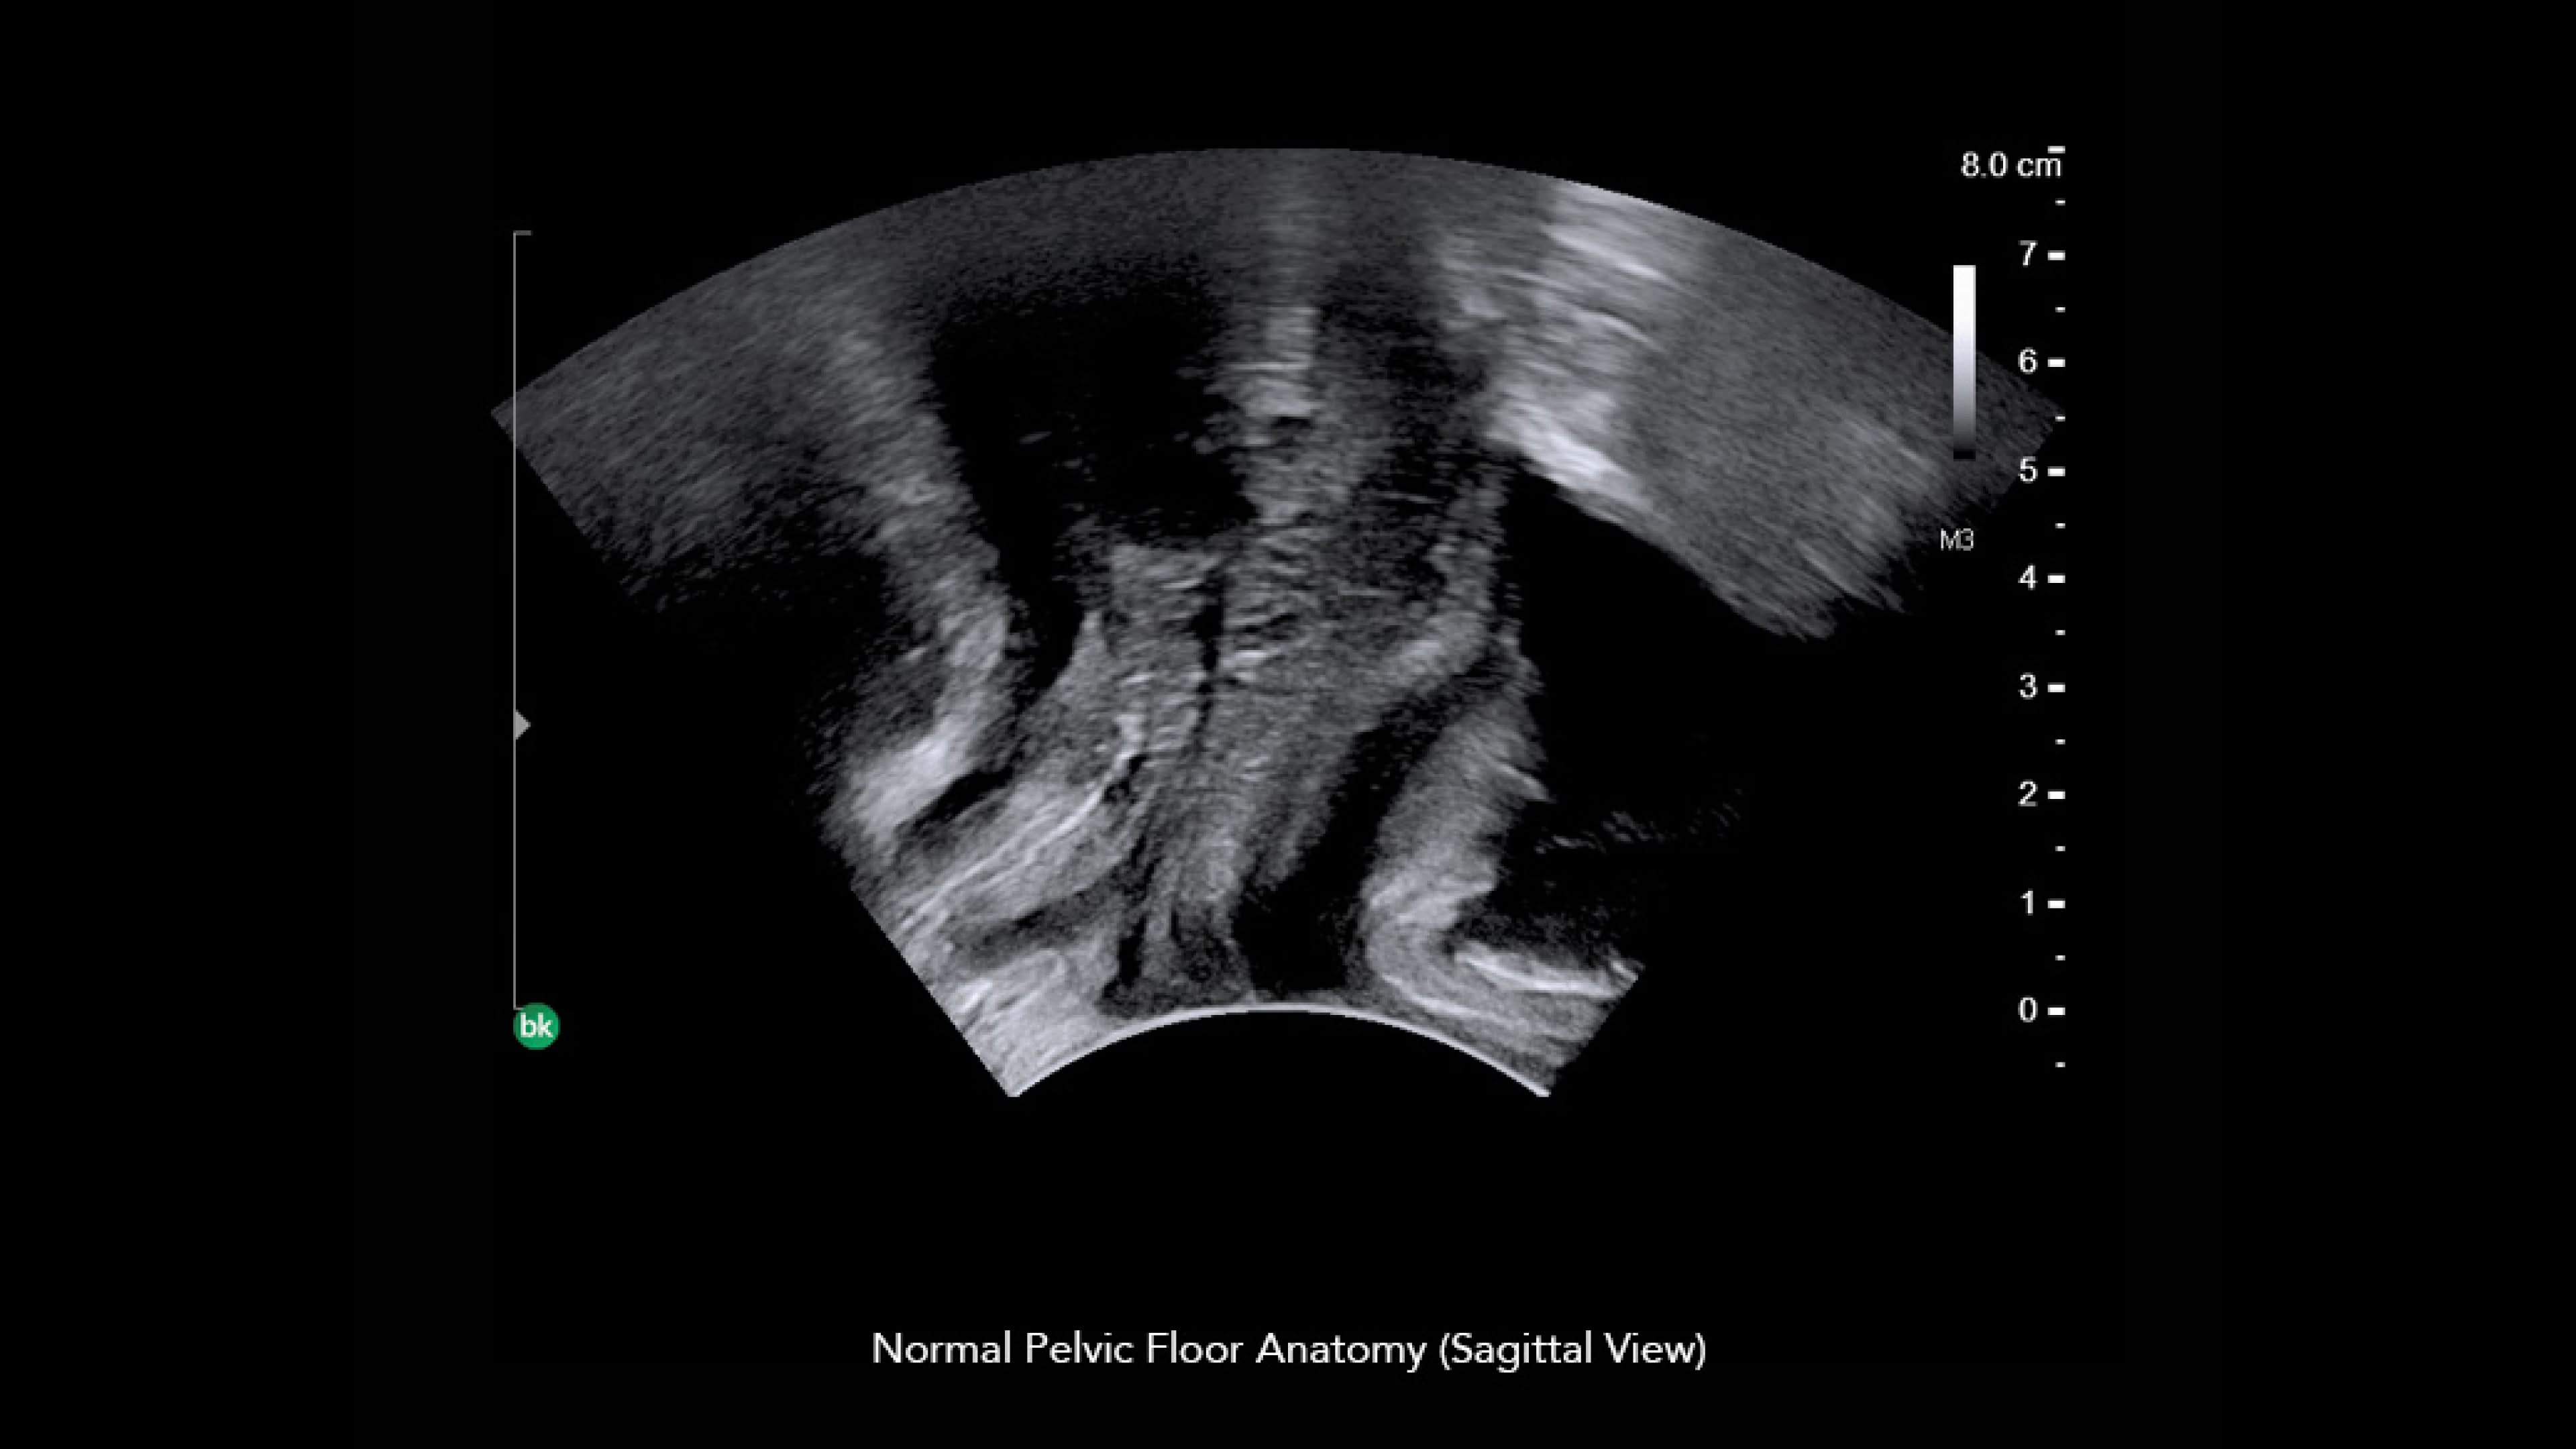

bkActiv Ultrasound System for General Surgery & Spine Procedures

Discover the bkActiv ultrasound system for enhanced visualization and precision in general surgery, neurosurgery, urology, colorectal, and pelvic floor procedures.